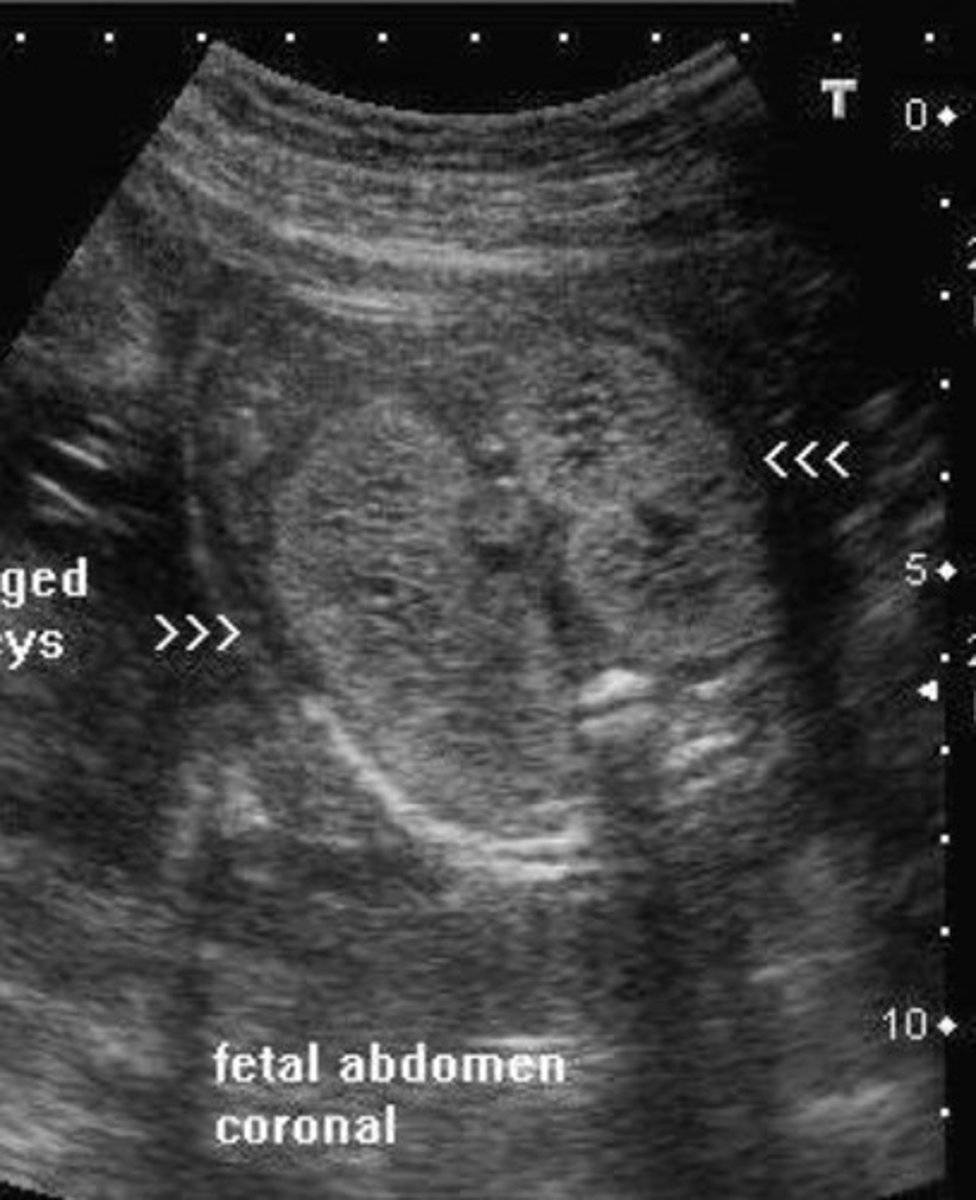

Potter's Syndrome Type III - Autosomal Dominant Polycystic Kidney Disease

Bilateral large cysts

Large kidneys

Hyperechoic parenchyma

Normal bladder/fluid levels